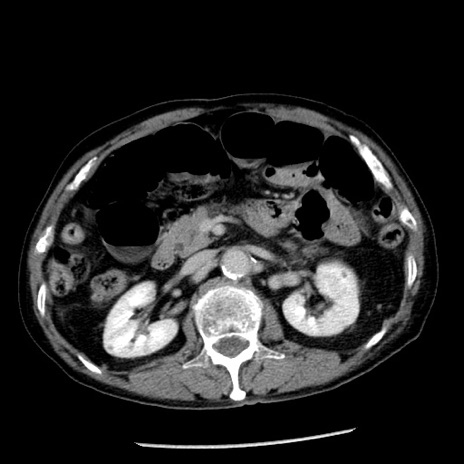

症例26(横断像)

【症例】80歳代男性

【主訴】嘔吐

【現病歴】昨晩2回嘔吐あり、今朝になっても嘔吐あり。来院。

【既往歴】胃潰瘍

【身体所見】意識清明、BT 37.6℃、BP 166/95mmHg、HR 100bpm、SpO2 97%、腹部:平坦・軟、腸蠕動音聴取良好、圧痛なし。

【データ】WBC 21900、CRP 1.46